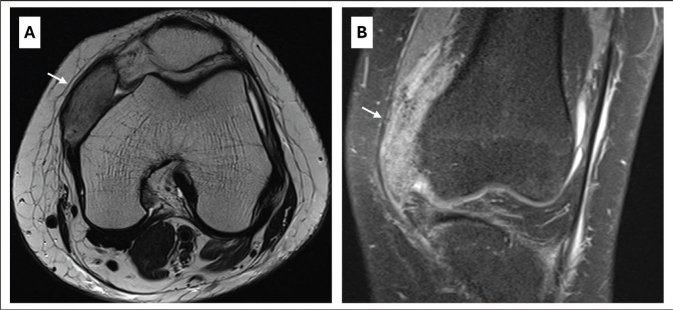

Case presentation: This case describes a young woman with no relevant previous medical history who developed severe bilateral heterotopic ossification on the anteromedial sides of her knees after an intensive care unit stay. Passive flexion of both knees was limited to 50°. X-ray was a simple diagnostic tool. Predisposing factors were extended immobilization, prolonged systematic inflammatory condition and mechanical ventilation. Due to the failure of initial conservative therapy, the heterotopic ossification was resected early, 4 months after onset of first symptoms. Following an intensive rehabilitation program, a normal, pain-free gait and full range of motion of both knees were achieved 9 months after surgery.